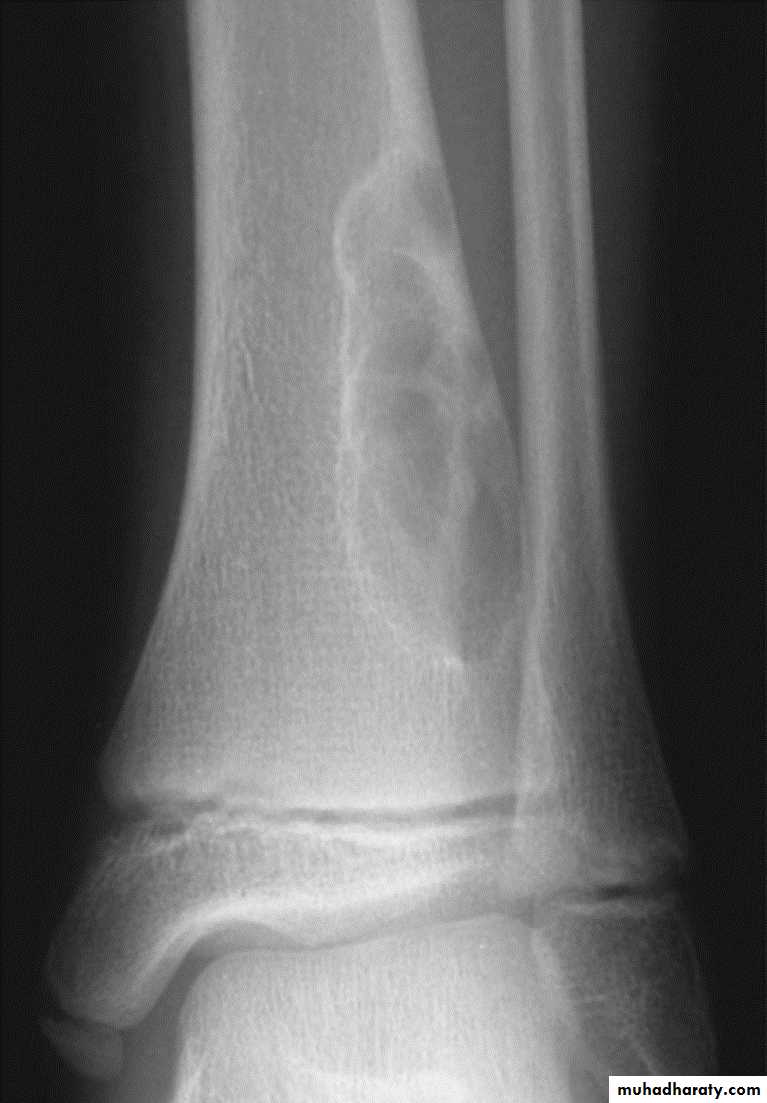

Osteochondroma of the distal femur.

The cortex is continuous with that of the underlying bone and trabecular bone merges with that of the femur. A well-defined cartilage cap contains calcification and is directedaway from the joint.